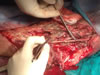

Brazo Catastrófico |

Intervención inicial - Reintervención por necrosis |